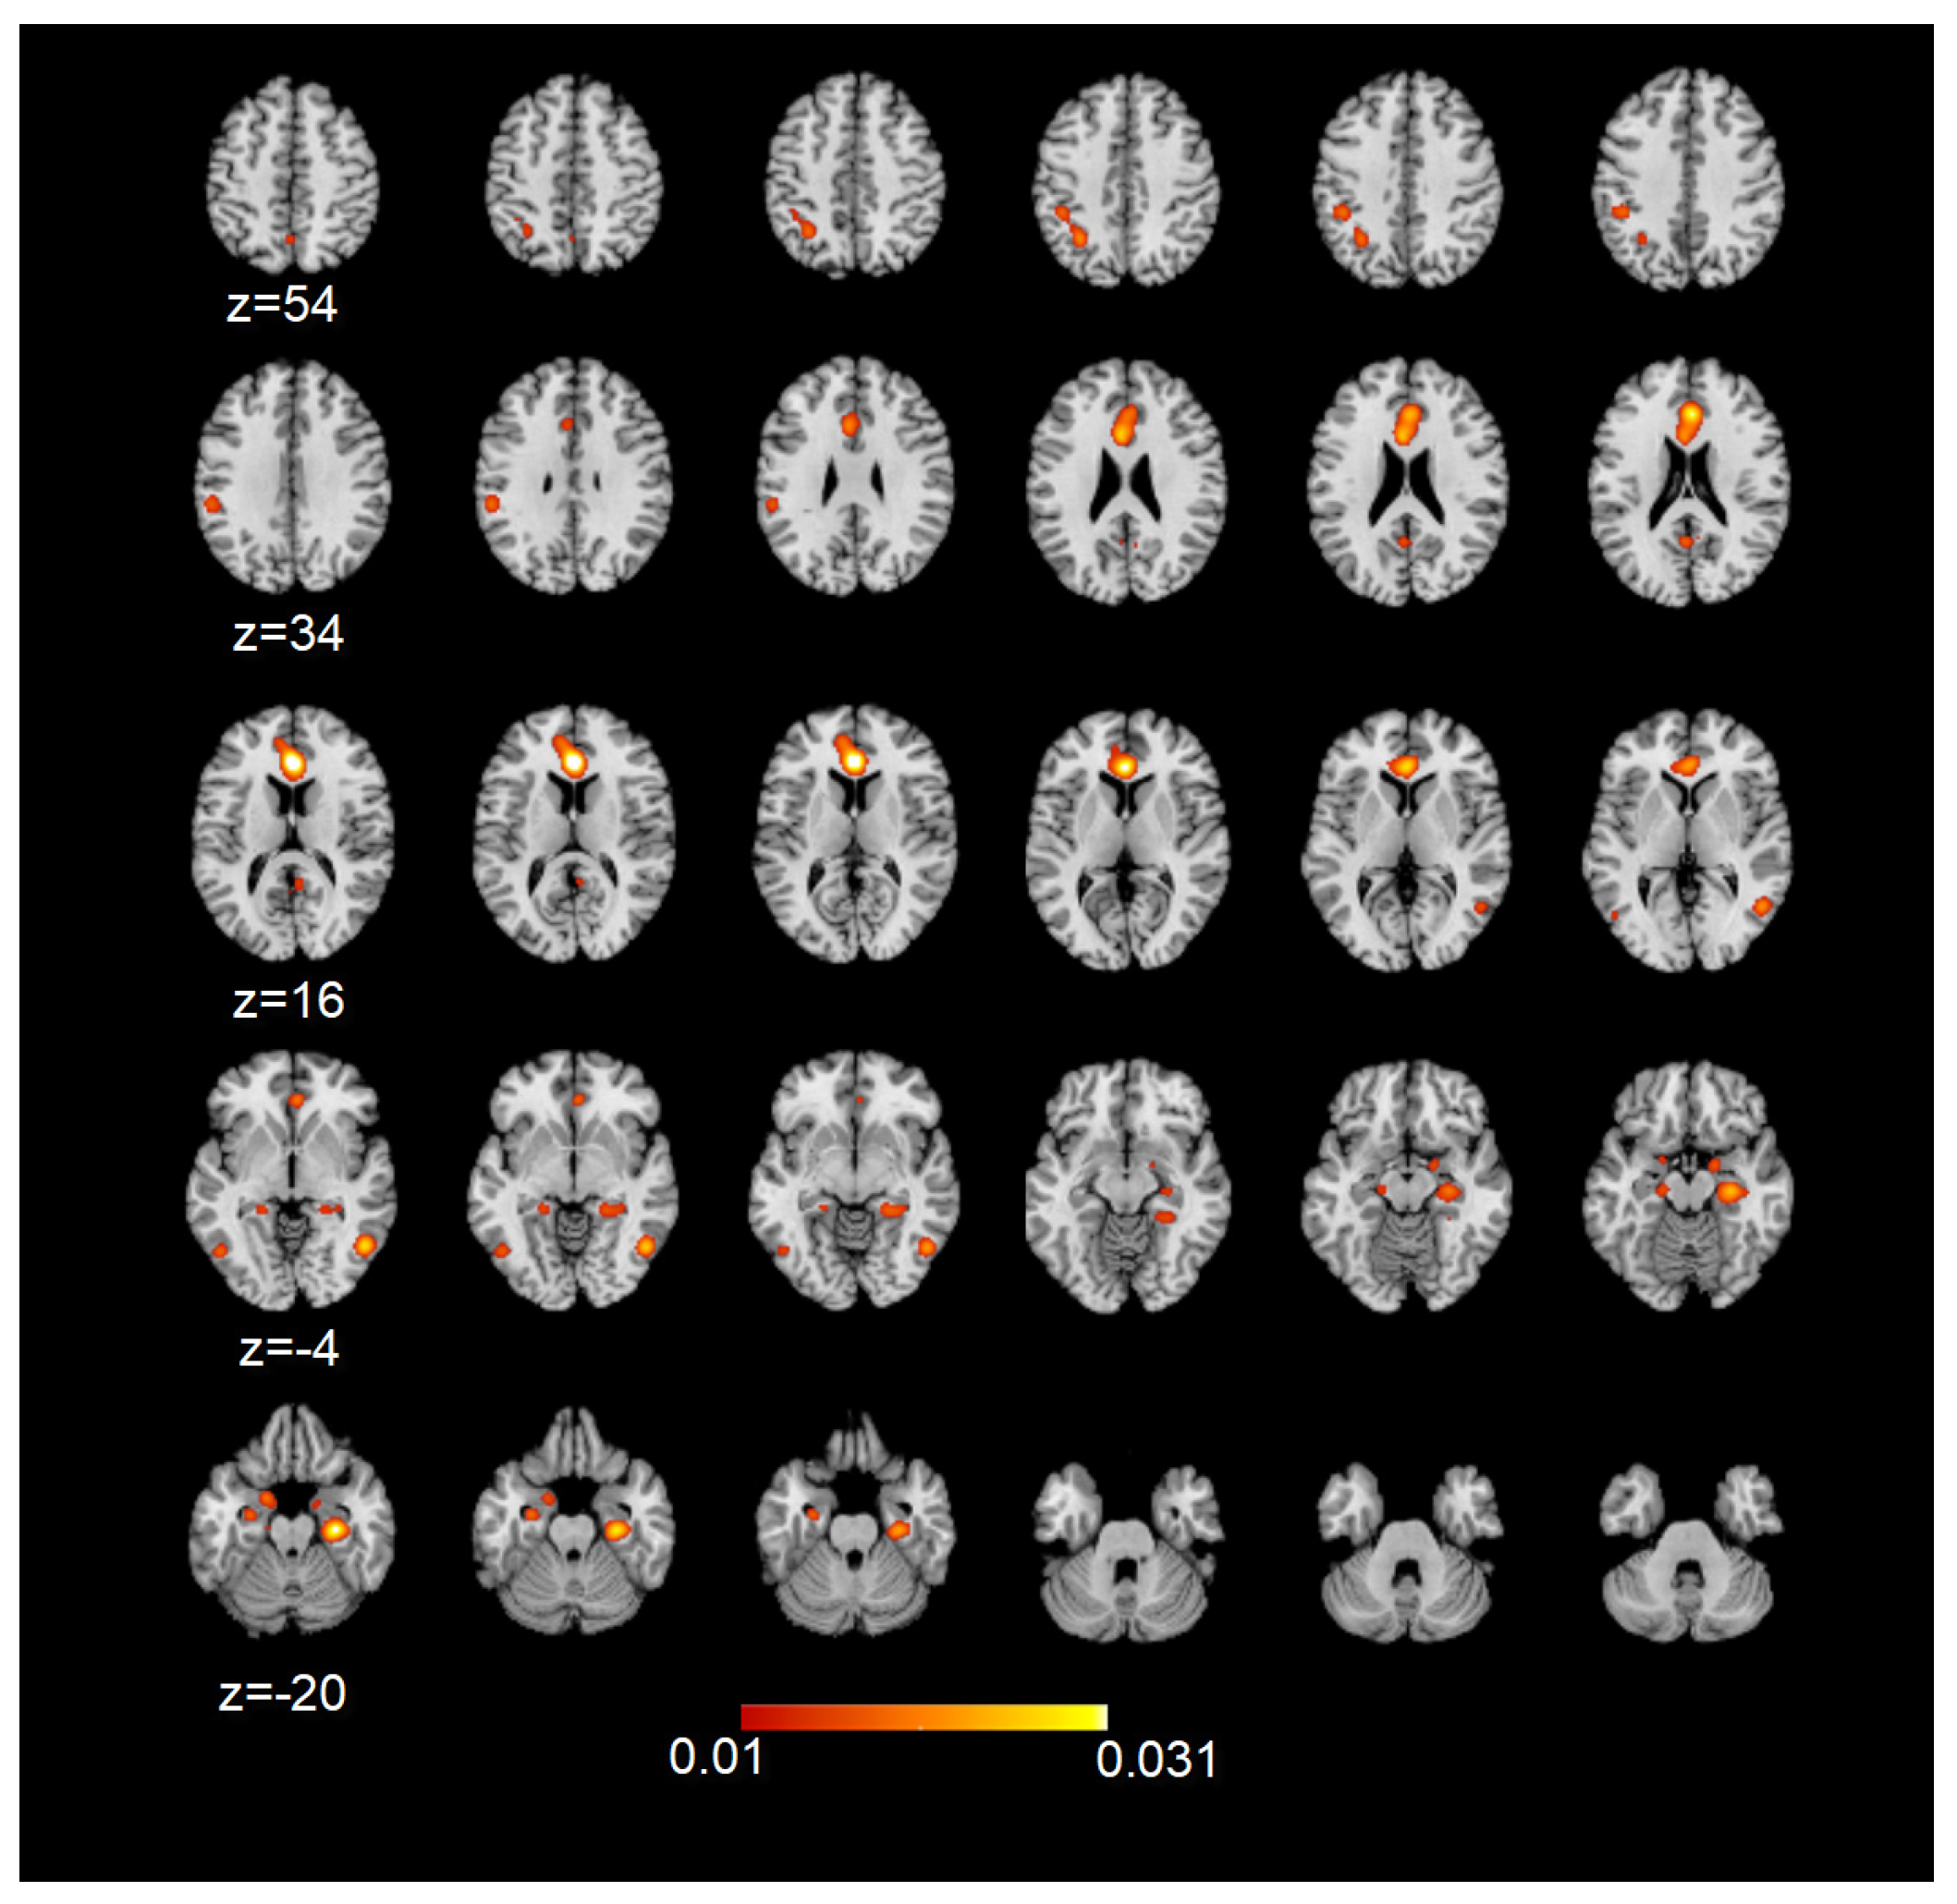

To assess the involvement of the DMN during sexual stimulation in healthy heterosexual participants or in specific populations or pathological conditions, we performed a series of meta-analyses, followed by conjunction analyses, which allowed for a comparison of the results. During sexual stimulation, all the principal nodes included in the DMN were involved. However, more homogeneous clusters, with higher ALE values, were found in correspondence with the ACC/mPFC and parahippocampal/hippocampi bilaterally (FDR pN < 0.01; Figure 3).

Figure 3.

ALE map of the resulting DMN nodes during sexual stimulation. Maps are overimposed on a 2 × 2 × 2 mm MNI template according to neurological convention. The colored bar denotes the corresponding ALE value ranges indicated on the maps (FDR pN < 0.01).